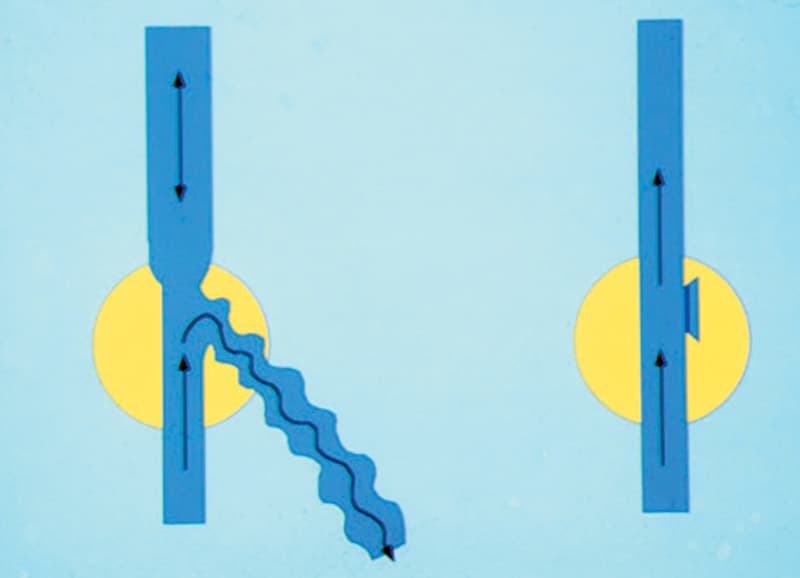

La crossectomie consiste à débrancher la communication principale entre le réseau superficiel et le réseau profond au niveau du pli de l’aine ou du creux du genou (racine de l’arbre).

Elle permet de fermer la fuite principale par une incision de quelques centimètres. Elle est peu souvent nécessaire.